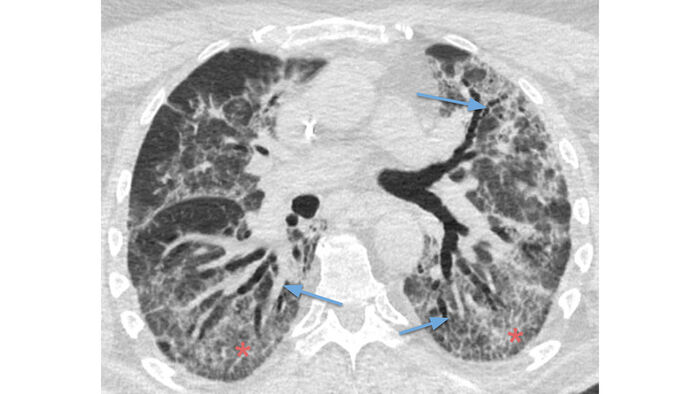

Mynd 2 TS-rannsóknir í bráðafasa og við eftirlit. Hver bókstafur táknar mismunandi sjúkling og mynd merkt i er í bráðum sjúkdómsfasa og mynd merkt ii er sama sneið í eftirliti.

Ai er af COVID-19 sjúklingi á 12. degi veikinda (TS-stig 19/25). Meirihluti lungnavefs er undirlagður af hélubreytingum (rauðar stjörnur) og bandlaga þétting aðlægt fleiðru er í hægra lunga (blá ör).

Á Aii í eftirliti 8 vikum síðar hafa íferðir hreinsast upp og engar langvinnar COVID-19 lungnabreytingar eru til staðar (TS-stig 0/25).

Bi er sjúklingur með alvarlegan COVID-19 á 30. degi veikinda. Á fyrri myndinni eru miklar íferðir enn til staðar þrátt fyrir að bráðafasi sjúkdómsins sé liðinn (TS-stig 23/25). Einnig eru til staðar berkjuskúlk (bláar örvar), hellulagnamynstur (rauðar stjörnur) og bandlaga þéttingar aðlægt fleiðrum.

Bii er tekin 6 vikum síðar (TS-stig 20/25) og eftir sitja trefjaðar (e. fibrotic) lungnabreytingar með breytingu á formgerð lungnanna þar sem íferðir voru mestar áður og berkjuskúlki (blá ör).

Ci er af COVID-19 sjúklingi á 13. degi veikinda og sýnir útbreiddar alþéttar íferðir (rauðar stjörnur) og hélubreytingar (blá ör) með TS-stig 25/25.

Cii er mynd fjórum mánuðum síðar. Þar sem áður voru þéttar íferðir eru nú þunnar bandlaga breytingar aðlægt fleiðrum (bláar örvar) ásamt daufum hélubreytingum. Því voru enn miklar lungnabreytingar til staðar þrátt fyrir langan tíma frá upphafi einkenna með útbreiðslustig 21/25.

Di er af COVID-19 sjúklingi á 30. degi veikinda og sýnir þykkar bandlaga breytingar við fleiðru aftantil í lungum (bláar örvar) og ekki teljandi hélubreytingar (TS-stig 20/25).

Dii er um 7 vikum síðar og eru bandlaga breytingarnar nú mun þynnri en áður. Einnig eru tilkomnar daufar hélubreytingar aðlægt þeim (bláar örvar) (TS-stig 14/25).

Ei er af COVID-19 sjúklingi á 24. degi veikinda með alþéttar íferðir og hélubreytingar ásamt hellulagnamynstri aftan til í öllum lungnablöðum (bláir hringir, TS-stig 24/25).

Eii er tekin tæplega tveimur mánuðum síðar. Engar bandlaga breytingar voru til staðar þá í lungum heldur mjög daufar en útbreiddar hélubreytingar (TS-stig 17/25).